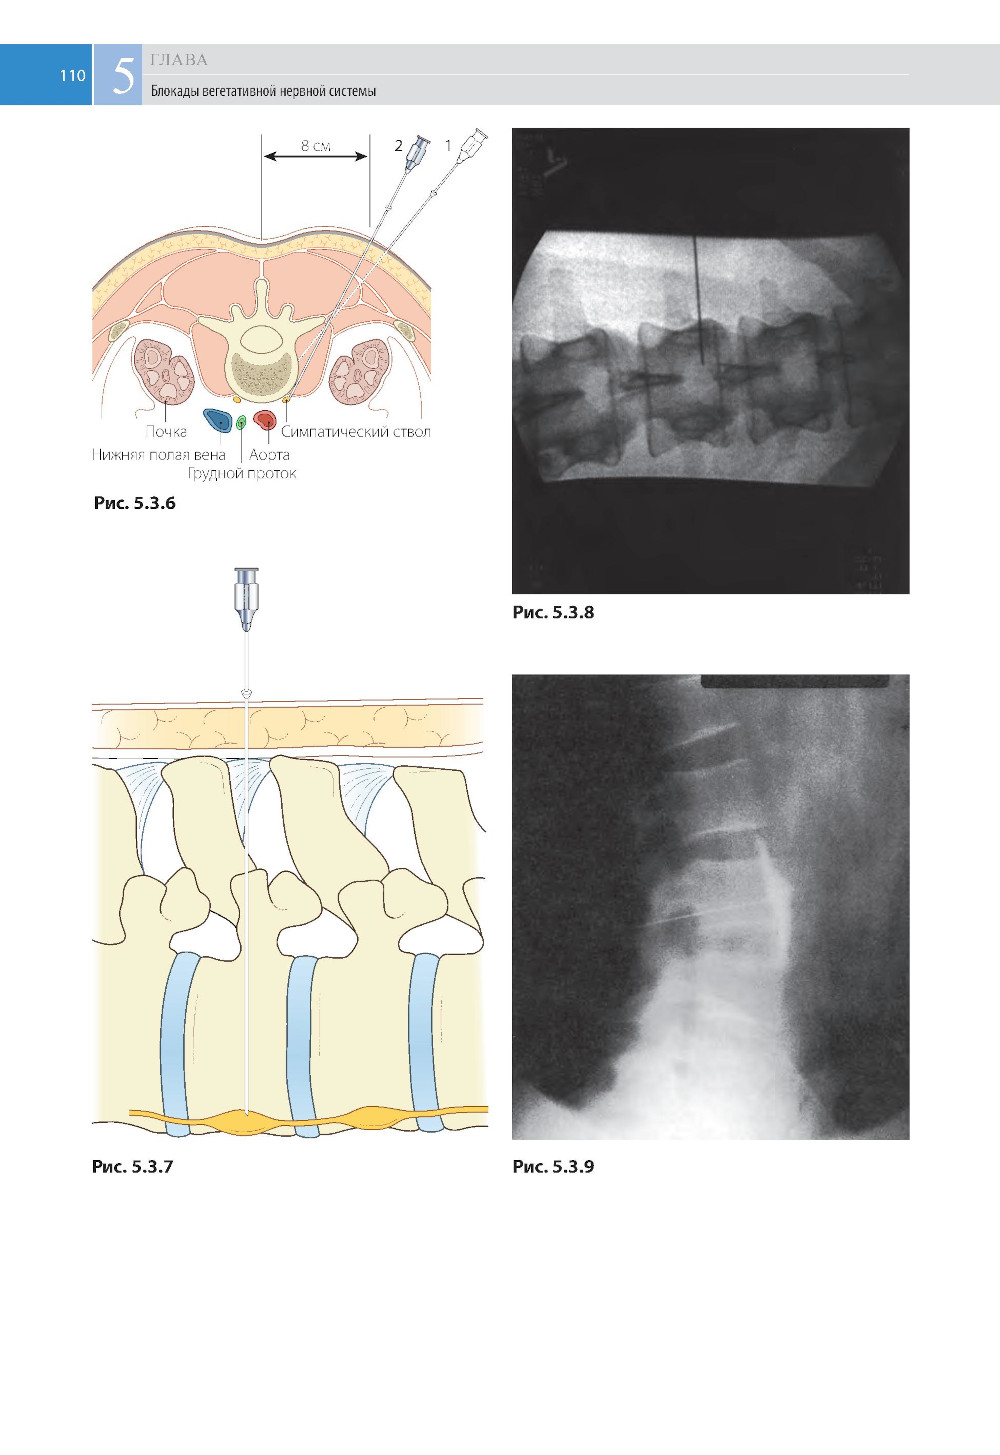

В «Атласе по инъекционным методам лечения боли» представлены методики часто применяемых внутрисуставных и внутримышечных инъекций и многих основных методов регионарной анестезии, которые уже многие годы входят в арсенал анестезиологов и применяются для устранения или облегчения длительной и интенсивной боли. Приводится пошаговое описание техники введения растворов местных анестетиков, кортикостероидов и нейролитических препаратов, богато проиллюстрированное наглядными рисунками анатомических структур и фотографиями. Приводятся возможные осложнения, особенно при сложных блокадах, требующих определенных навыков (перидуральной, звездчатого узла, чревного сплетения и др.), и рекомендации по их предупреждению. Книга предназначена для врачей, которые сталкиваются в своей практической деятельности с проблемой лечения боли, в том числе посттравматической, послеоперационной, миофасциальной и боли при онкологической патологии.| Издательство | МЕДпресс-информ |